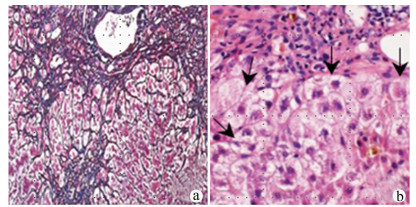

Effect of polarized bone marrow-derived macrophage transplantation on the progression of CCl4-induced liver fibrosis in rats

Xun JIAN, Danyang WANG, Yannan XU, Jiamei CHEN, Wei LIU, Gaofeng CHEN, Hua ZHANG, Ping LIU, Yongping MU

2021, 37(12): 2830-2837. DOI: 10.3969/j.issn.1001-5256.2021.12.020

Abstract(2318) HTML (1073) PDF (6875KB)(130)

Abstract:

Objective  To investigate the effect of polarized bone marrow-derived macrophage (BMDM) transplantation on the progression of CCl4-induced liver fibrosis in rats.  Methods  Rat BMDMs were isolated and induced to differentiate into M1 phenotype (M1-BMDM) by lipopolysaccharide (5 ng/mL) or M2 phenotype (M2-BMDM) by the supernatant of L929 cells. A rat model of liver fibrosis was established by subcutaneous injection of 30% CCl4 for 6 weeks, and at week 7, the model rats were randomly divided into model control group (M group), M1-BMDM group, and M2-BMDM group and were given a single injection of normal saline, M1-BMDM, and M2-BMDM, respectively, via the caudal vein, and subcutaneous injection of 30% CCl4 was given until the end of week 9. Related indices were observed, including liver function, liver histopathology, hydroxyproline (Hyp) content in liver tissue, hepatic stellate cell activation, liver fibrosis, and expression of inflammatory cytokines. The continuous data were expressed as mean±standard deviation; an analysis of variance was used for comparison between multiple groups, and the SNK-q test was used for further comparison between two groups.  Results  Compared with the M group, both M1-BMDM and M2-BMDM significantly inhibited liver inflammation and liver fibrosis progression and significantly reduced serum alanine aminotransferase and aspartate aminotransferase activities (P < 0.01) and Hyp content in liver tissue (P < 0.05). M1-BMDM and M2-BMDM significantly inhibited the activation of hepatic stellate cells and significantly reduced the mRNA expression levels of TGF-β, Col1A1, and Col4 (all P < 0.05). Both M1-BMDM and M2-BMDM significantly increased the expression level of CD163 protein in liver tissue (P < 0.01), and the M2-BMDM group had a significantly higher level than the M1-BMDM group (P < 0.05); both M1-BMDM and M2-BMDM significantly reduced the mRNA expression levels of MMP-2 and TIMP-1 in liver tissue (P < 0.05) and significantly increased the mRNA expression level of MMP-13 (P < 0.01); in addition, M2-BMDM significantly reduced the expression level of CD68 protein in liver tissue (P < 0.01). Both M1-BMDM and M2-BMDM significantly increased the mRNA expression levels of IL-6 and IL-10 and the protein expression level of albumin in liver tissue (all P < 0.05), and the above indices in the M2-BMDM group were significantly higher than those in the M1-BMDM group (all P < 0.05).  Conclusion  Both M1-BMDM and M2-BMDM can effectively inhibit the progression of CCl4-induced liver fibrosis in rats, possibly by inhibiting the activation of hepatic stellate cells and promoting the activation of anti-inflammatory macrophages. Moreover, M2-BMDM can also inhibit the activation of pro-inflammatory macrophages and thus has a better comprehensive intervention effect than M1-BMDM.